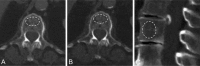

Methods: 200 patients, who had been randomly selected for an audit of CT reporting of incidental vertebral fractures, had their L1 density measured on 864 routine CT examinations. These had been performed with a variety of kVp and intravenous (i.v.) contrast protocols, reflecting the wide range of imaging indications.

Results: L1 density measured on thick axial, thin axial or sagittal images had an excellent intraclass correlation coefficient (0.996). For the same patients imaged twice within 6 months, there was mean intraexamination L1 density difference of 27.5 HU. Variability due to i.v. contrast medium administration resulted in a mean difference of 24.5 HU. Mean difference due to acquisition kVp was 24.1 HU. Once matched for sex, age, kVp and i.v. contrast, there was a significant difference between the L1 density in patients with vertebral fractures compared to those without fractures (mean 30.19 HU).